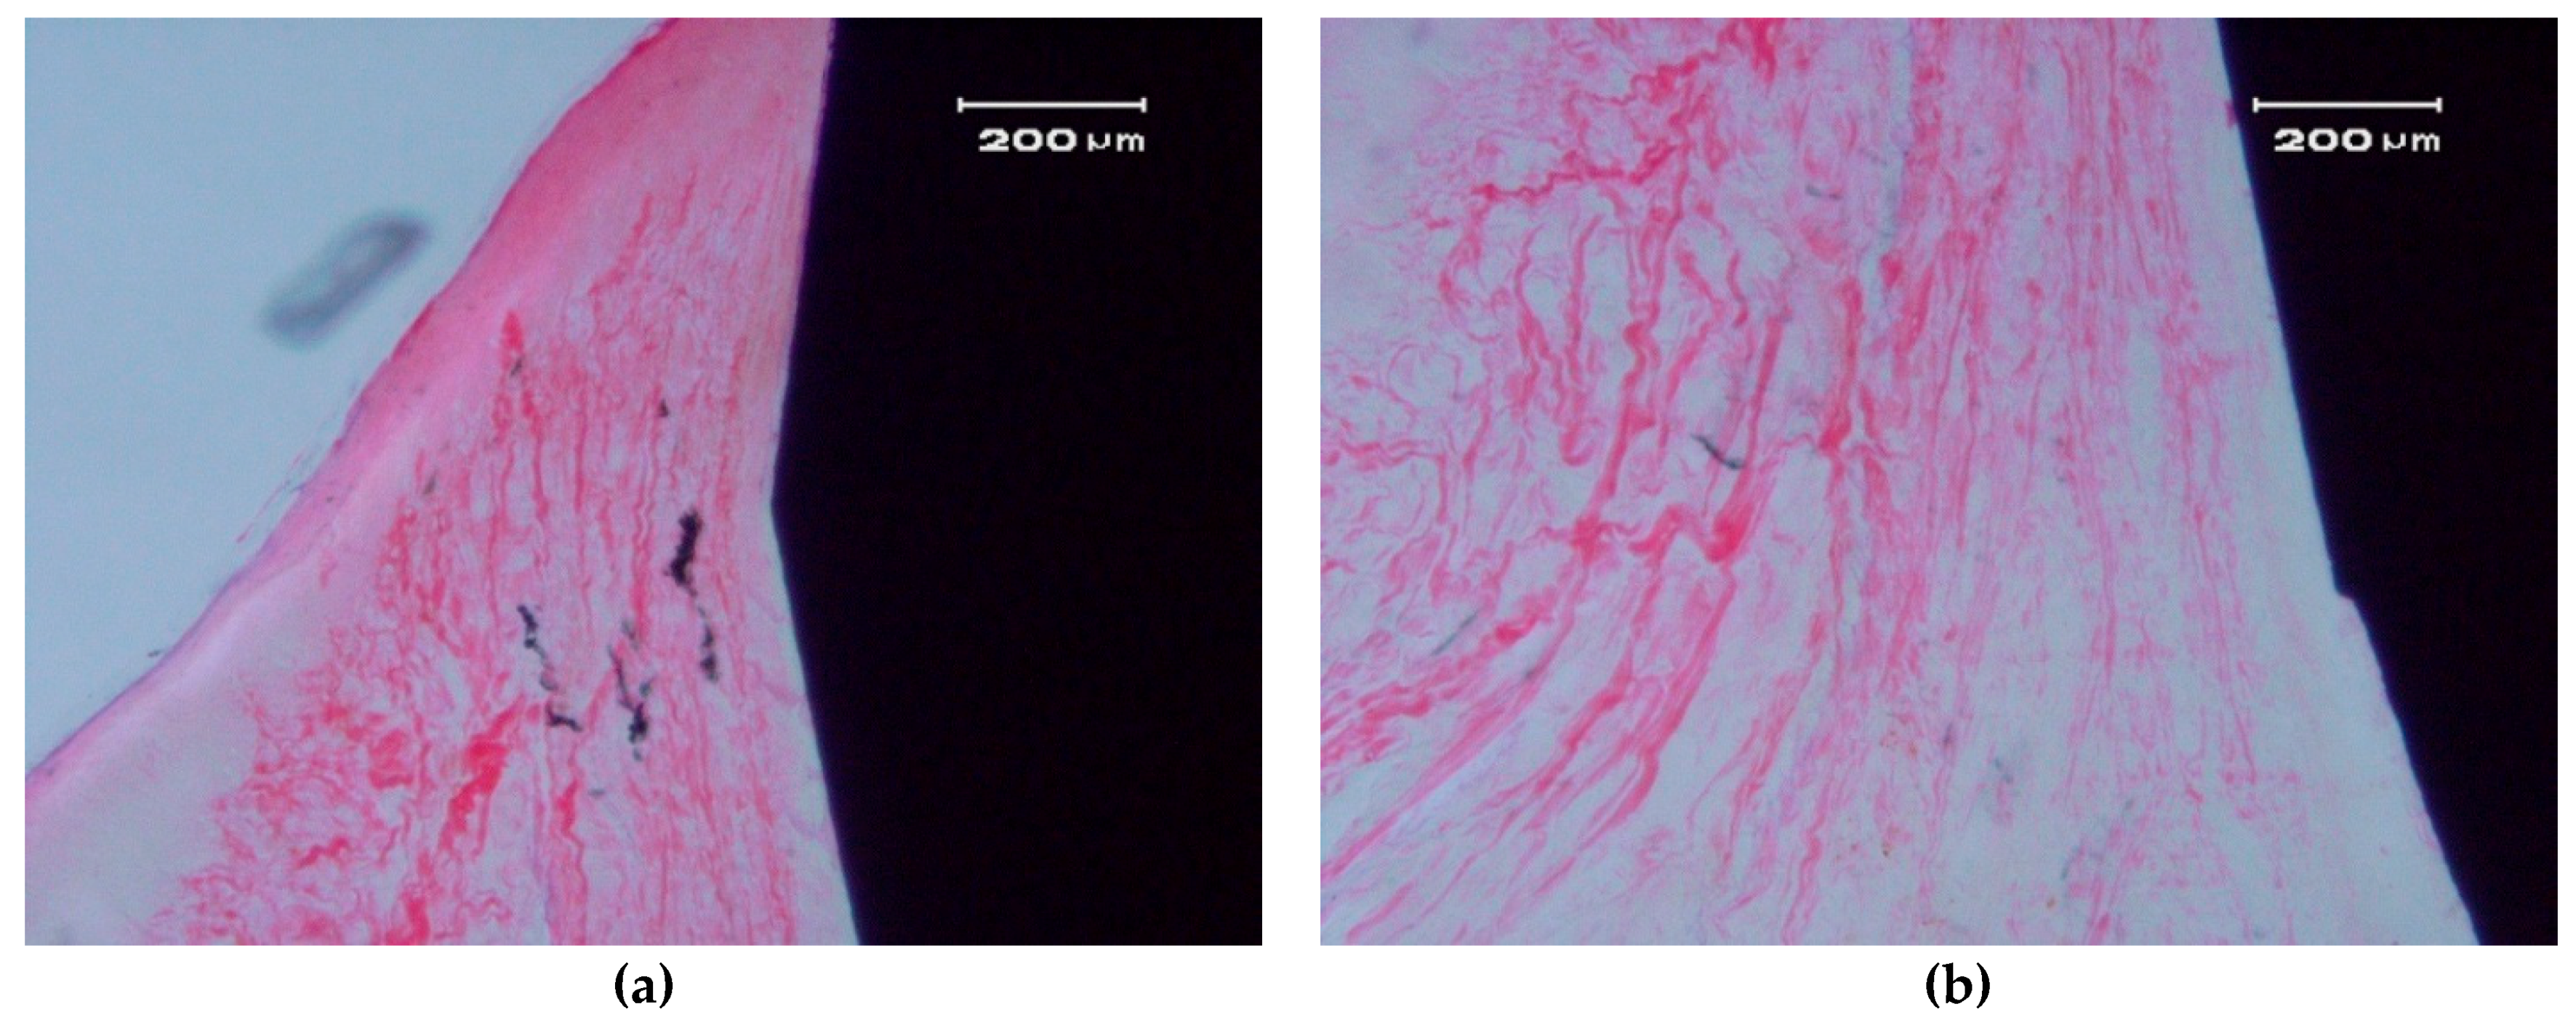

Figure 7.

Contact between a ZCe-A nanocomposite implant and soft gingival peri-implant tissue after eight weeks of healing (longitudinal cross-section). (a,b) show two different interfaces.

The soft, gingival, peri-implant tissue is found to be in perfect contact with the implant. There is a close epithelial adhesion to the implant surface (Figure 7a) without lymphocytic infiltrate, disruption of the keratinized gingival structure, or alterations of the connective tissue attachment (Figure 7b). Secondary and tertiary osteons and vascular buds are seen nearby the implant’s surface (Figure 7a). Bone grows inside the thread’s valleys in intimate contact with the implant and very clear reversal lines can be observed delineating the different stages of bone remodeling (Figure 7b). There are no signs of inflammation or implant rejection by the bone, nor atypia or dysplasia.